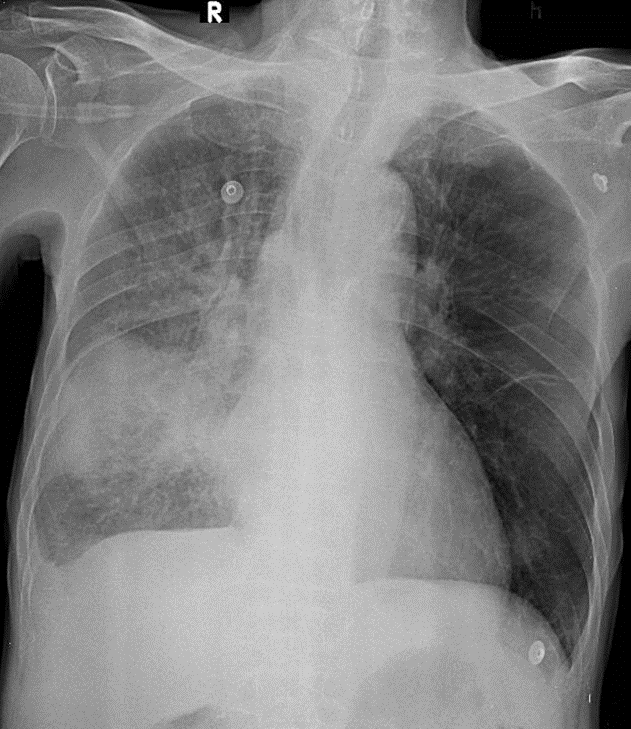

Hãy phân tích tình huống NAM 75 tuổi -CĐ:Viêm phổi, đợt cấp COPD nhóm d, bttmcb,hội chứng cushing do thuốc

1-Khí quản lệch (P) 2-Viêm phổi (P) lan tỏa 3-Tràn dịch màng phổi (P) 4-Cung động mạch chủ đóng vôi